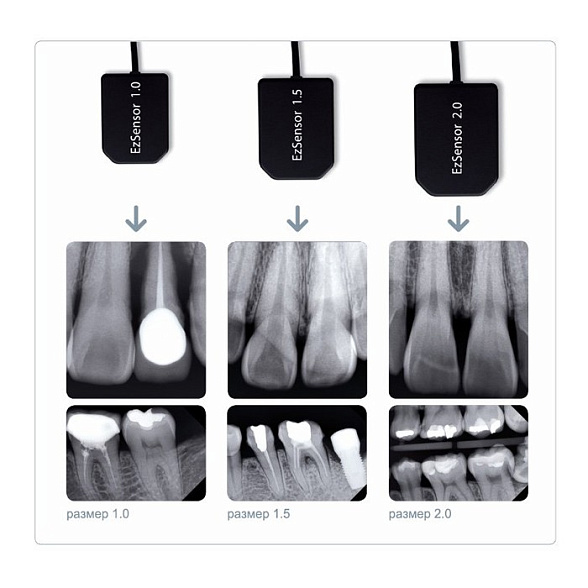

| Активная площадь сенсора | Приблизительно 37.5 мм x 25.5 мм (соответствует размеру сенсора №2) |

| Разрешение сенсора | Высокое, обеспечивающее детализированное изображение (точное значение lp/mm уточняйте у производителя) |

| Глубина цвета | До 16 бит (65536 оттенков серого) |

| Толщина датчика | Оптимизирована для комфорта пациента (около 5.5 мм) |